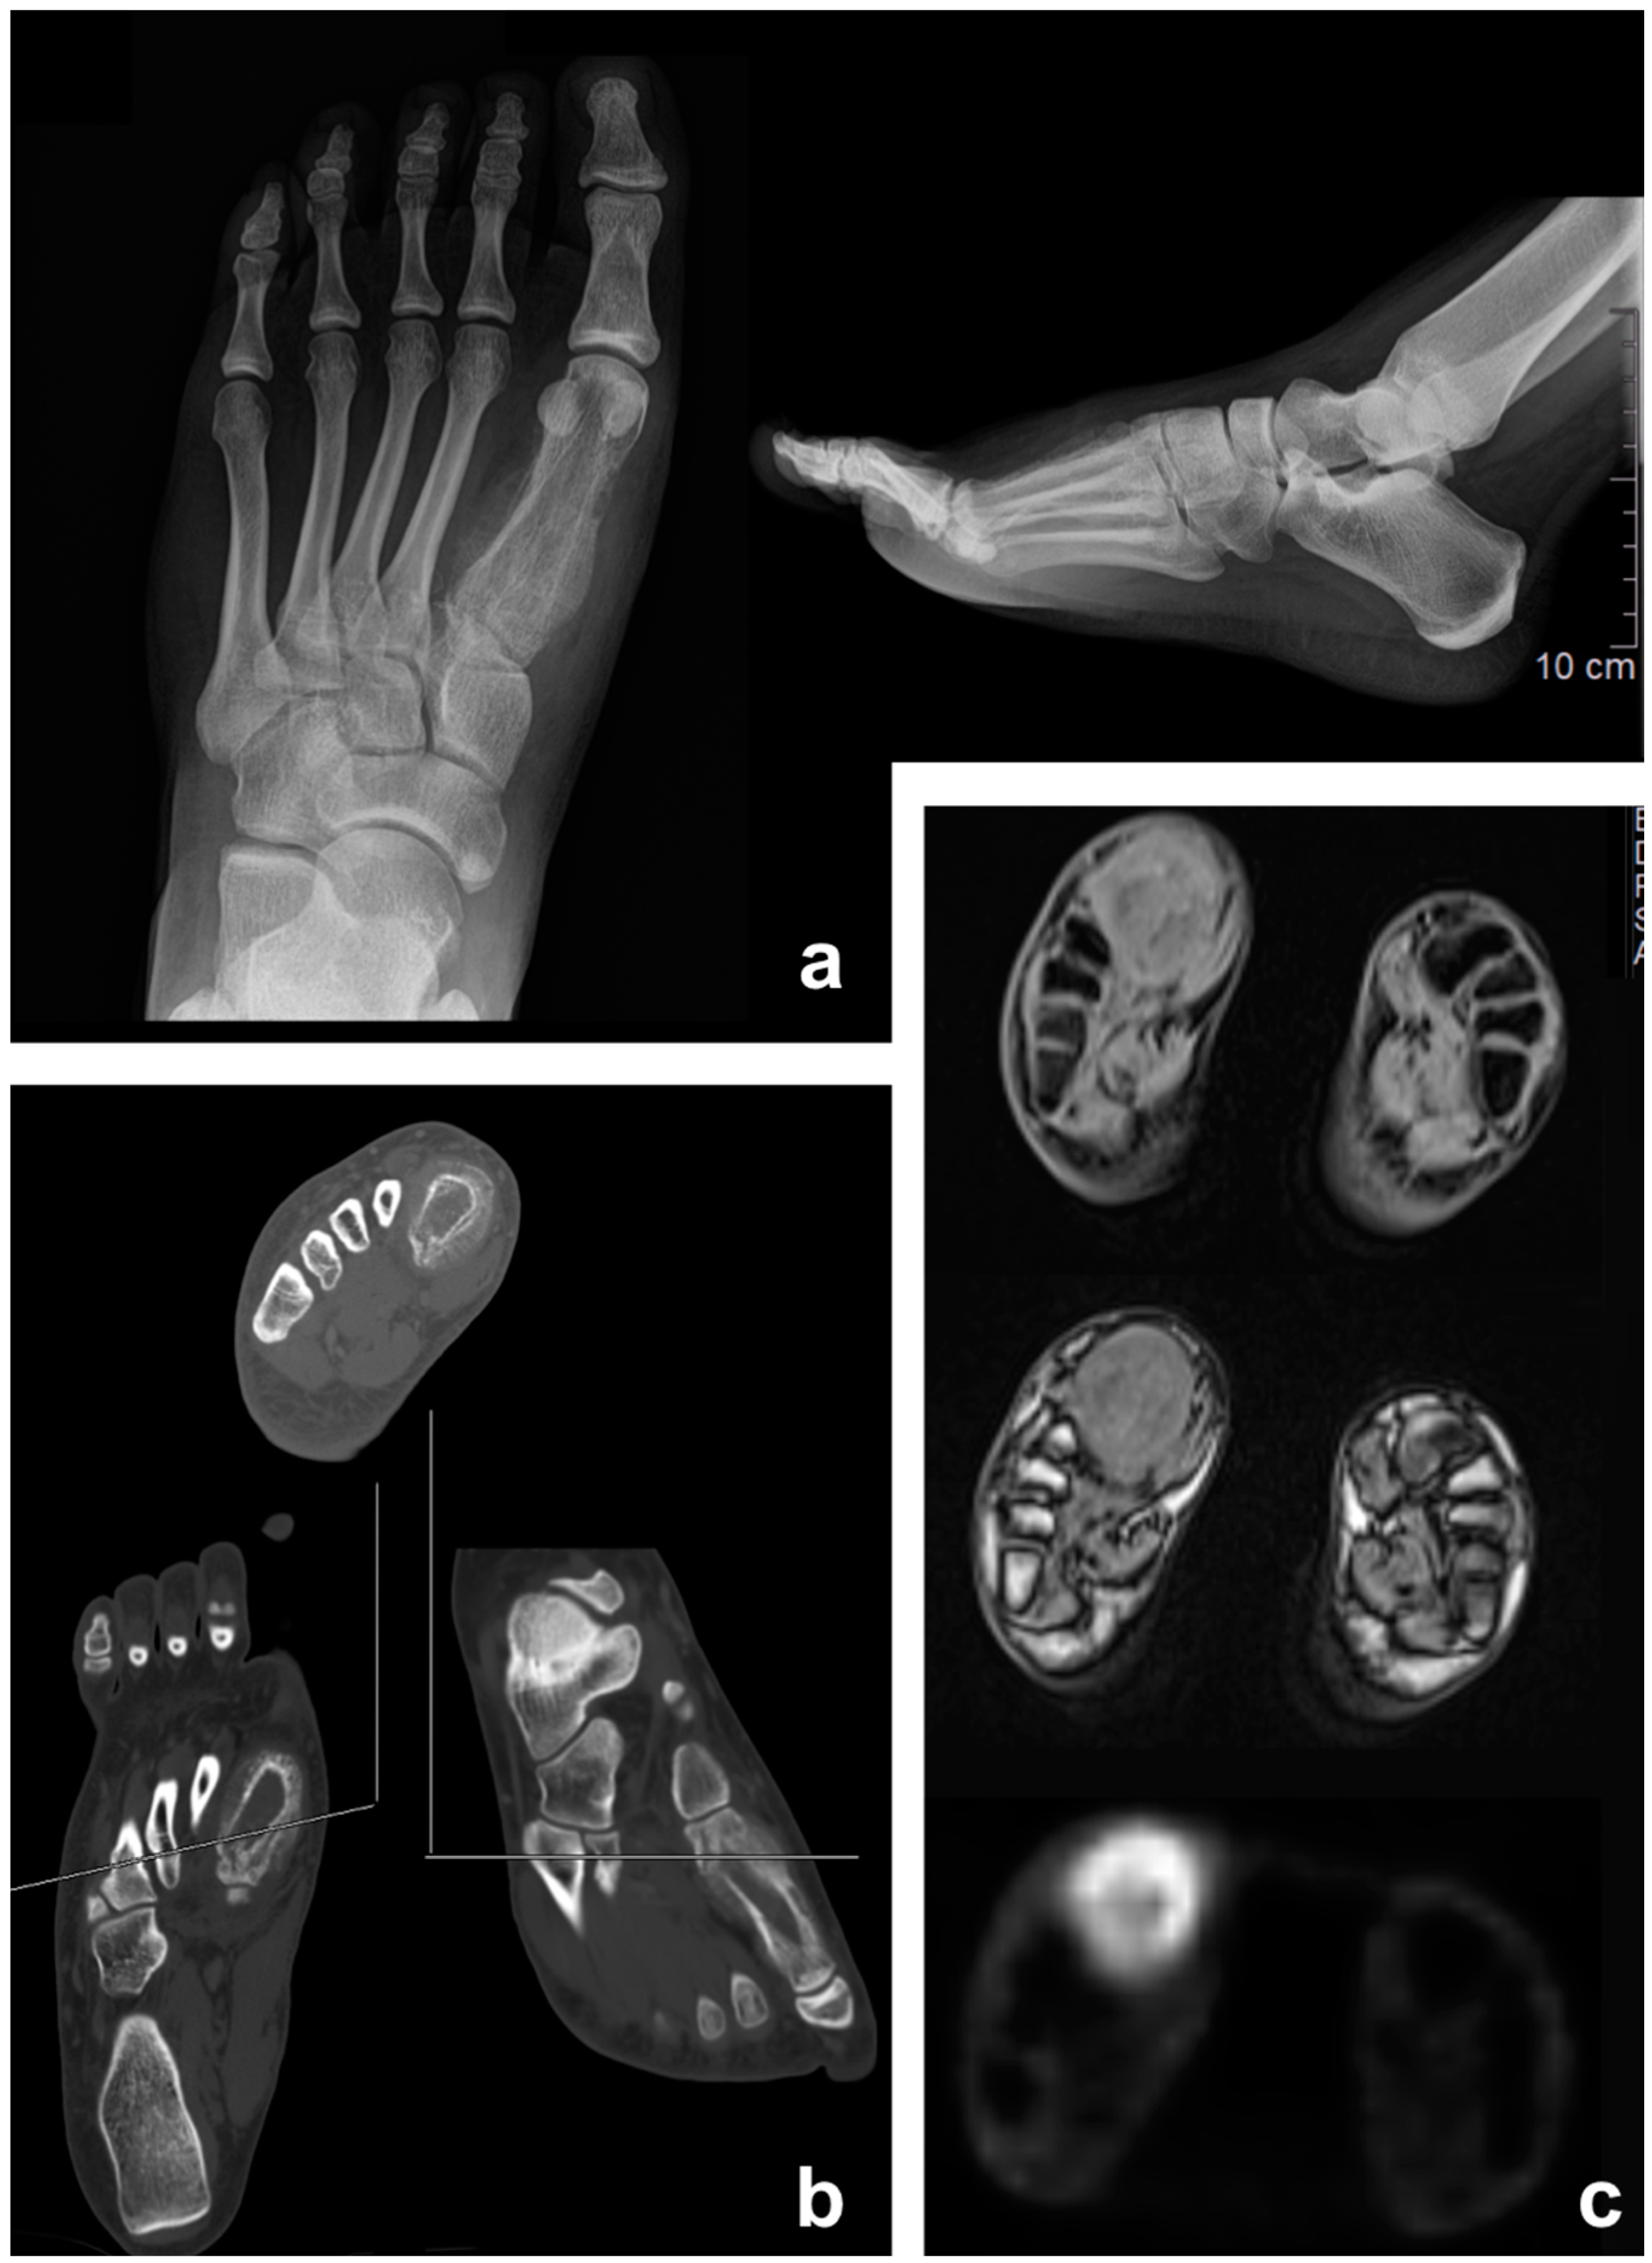

3.1. Osteosarcoma

3.2. Chondrosarcoma